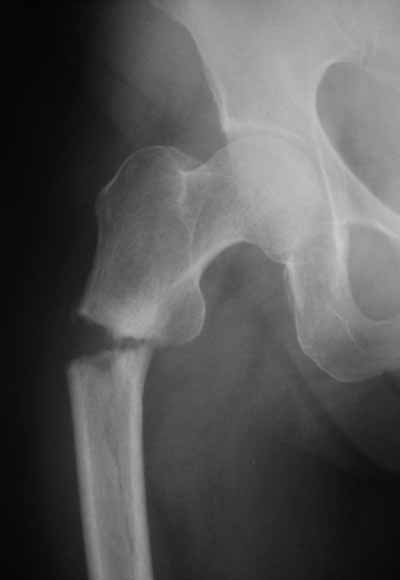

Да? Качество рентгенограмм конечно неочень, но ведь это нестабильный перелом 31.А2.2, не так ли?

> Да? Качество рентгенограмм конечно неочень, но ведь это

> нестабильный перелом 31.А2.2, не так ли?

Ну, после помещения туда такого гвоздя даже без дистального винта заметной нестабильности уже не остается ;-)